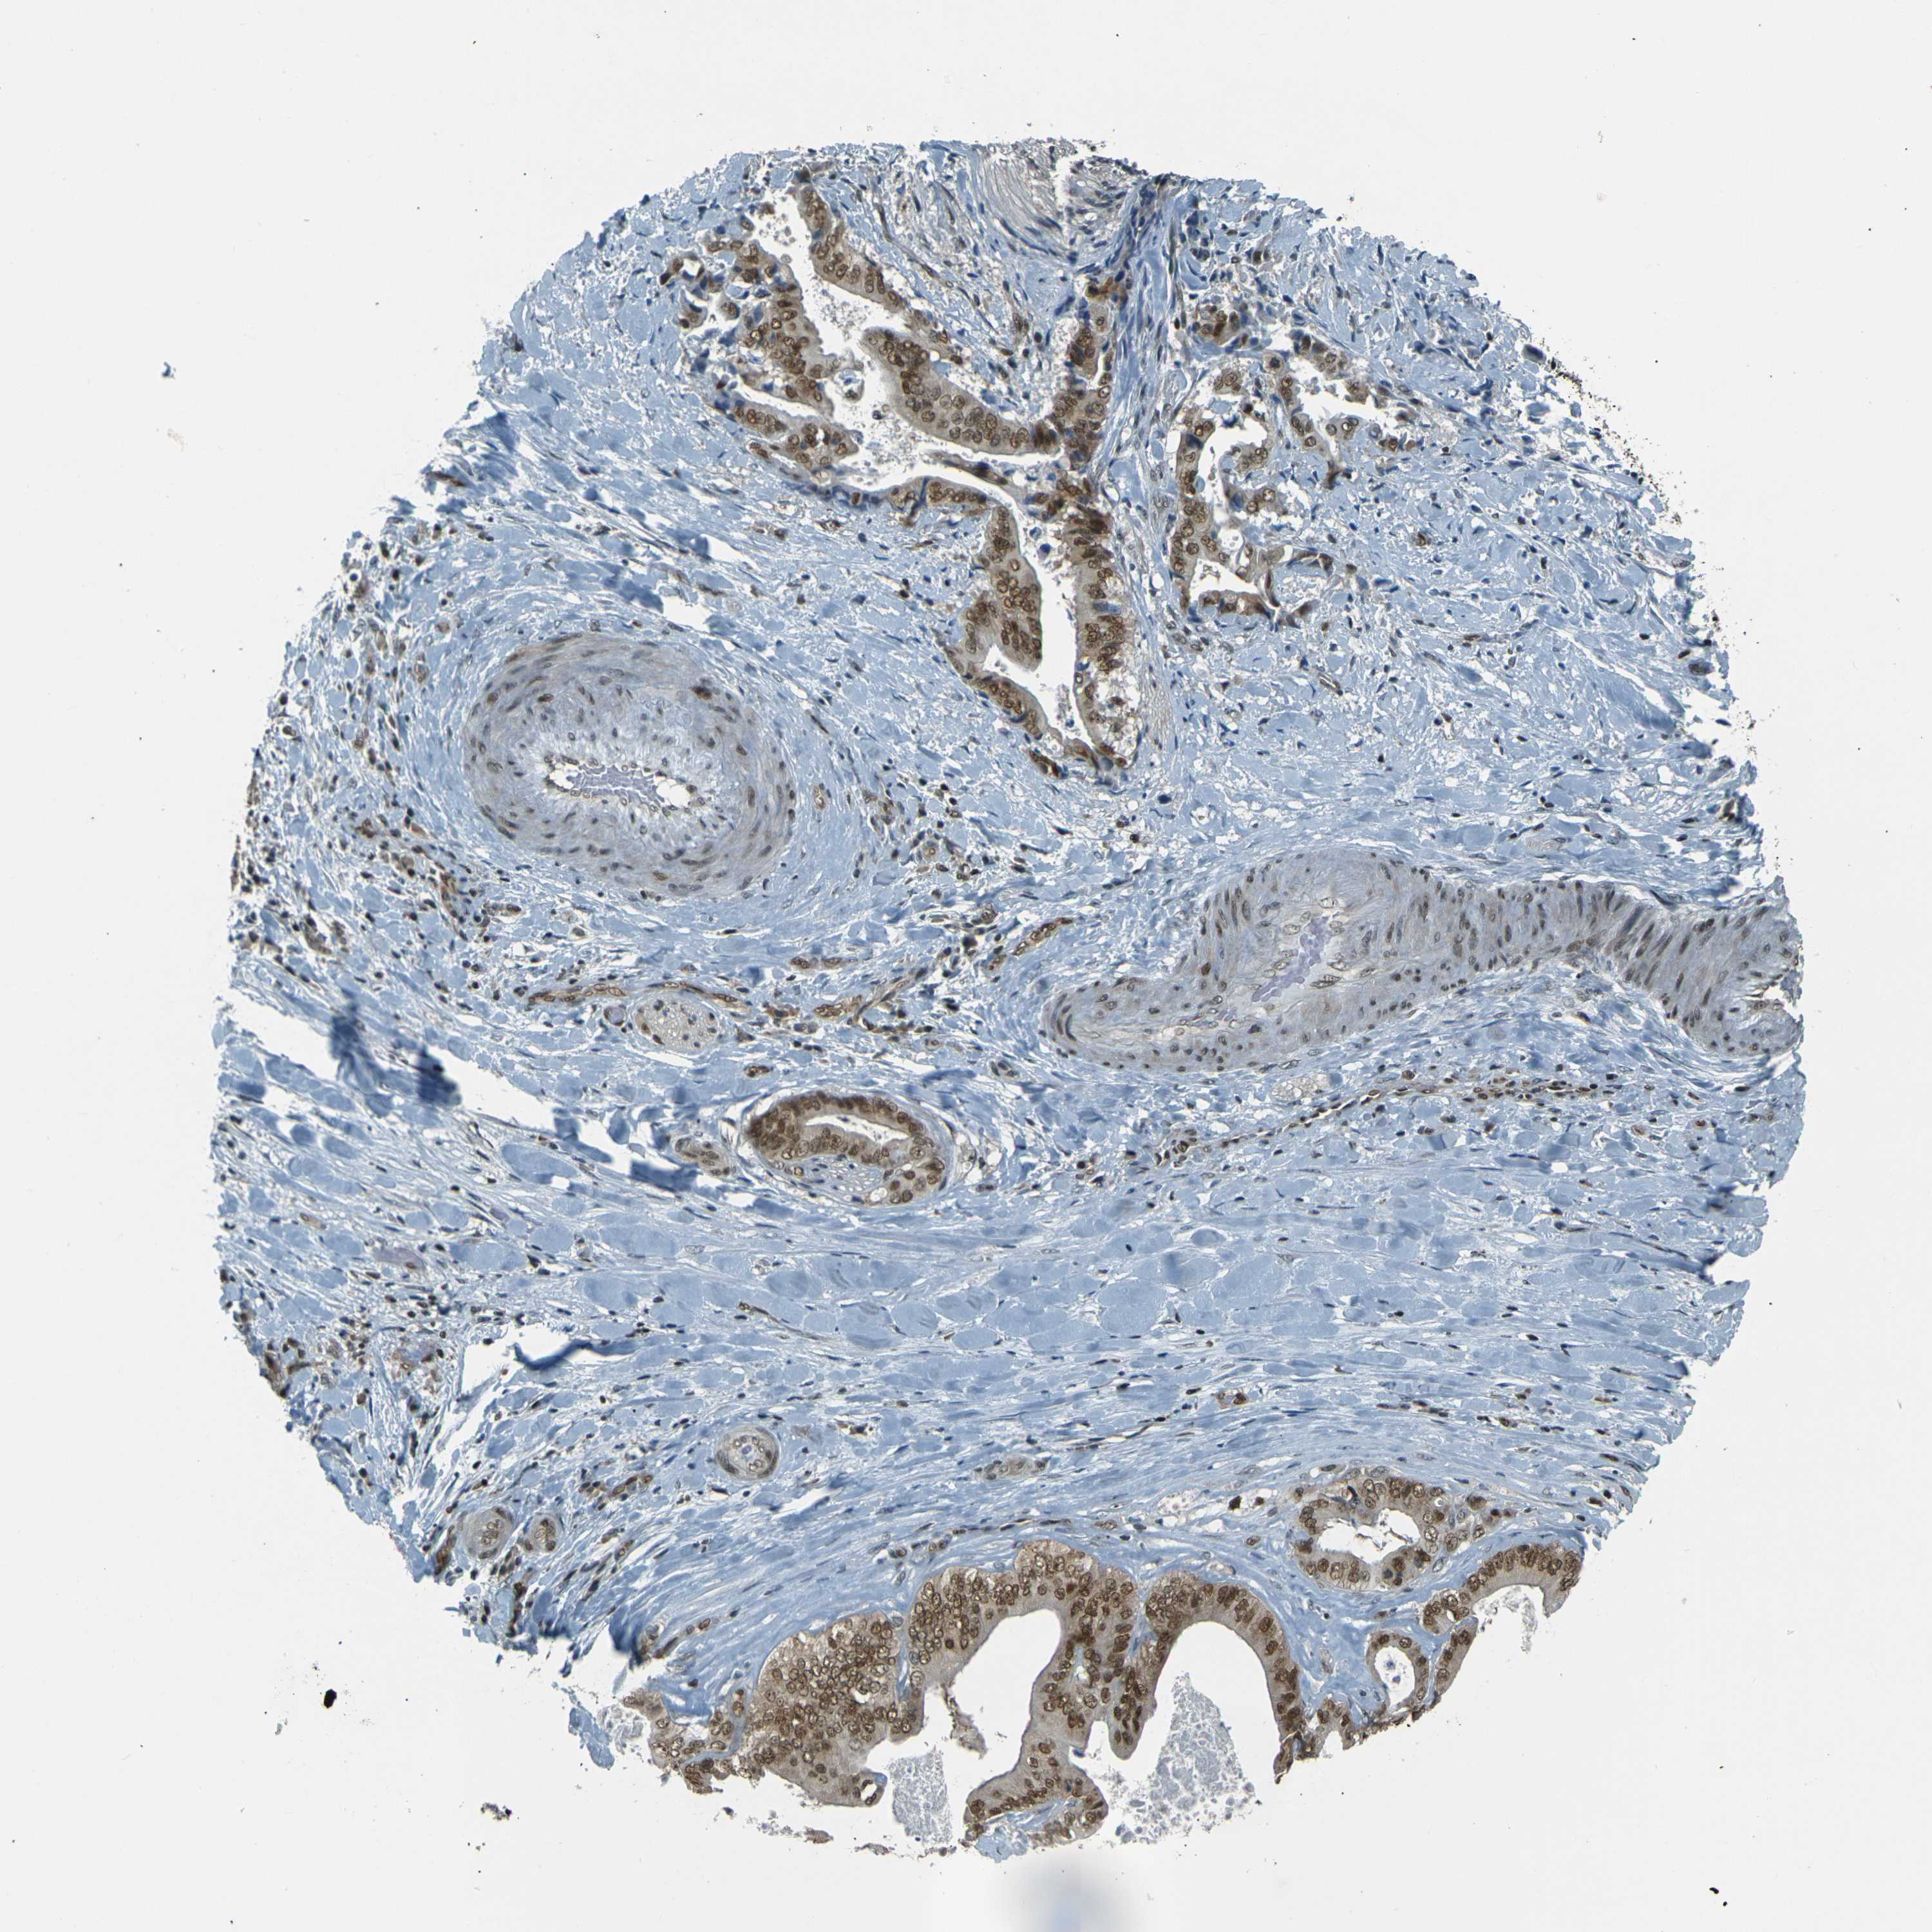

LIVER CANCER - Protein expressioni

A mouse-over function shows sample information and annotation data. Click on an image to view it in a full screen mode. Samples can be filtered based on level of antibody staining by selecting one or several of the following categories: high, medium, low and not detected. The assay and annotation is described here.

Note that samples used for immunohistochemistry by the Human Protein Atlas do not correspond to samples in the TCGA dataset.

Antibody stainingi

Antibody staining in the annotated cell types in the current human tissue is reported as not detected, low, medium, or high, based on conventional immunohistochemistry profiling in selected tissues. This score is based on the combination of the staining intensity and fraction of stained cells.

Each image is clickable and will lead to virtual microscopy that enables deeper exploration of all samples and also displays staining intensity scores, fraction scores and subcellular localization as well as patient and tissue information for each sample.

Antibody CAB012334

Staining

High

Medium

Low

Not detected

Intensity

Strong

Moderate

Weak

Negative

Quantity

>75%

75%-25%

<25%

None

Location

Nuclear

Cytoplasmic/membranous

Cytoplasmic/membranous,nuclear

Cholangiocarcinoma

Carcinoma, Hepatocellular, NOS